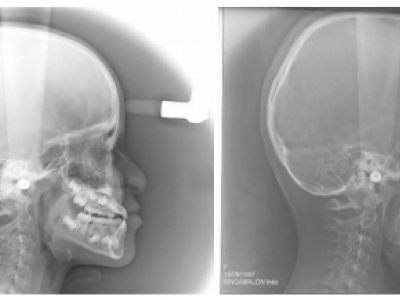

La projection mandibulaire est toujours plus marquée sur la téléradiographie qui est en occlusion (Fig. 11-16), que sur la photo, en position de repos, donc en inocclusion, avec une situation un peu plus reculée de la mandibule. Sur la radiographie panoramique, le manque de place est plus important à l’arcade supérieure, témoignant du manque de développement de cette structure. L’expansion tridimensionnelle de l’arcade donnera de la place aux dents permanentes.

Le patient est revu en denture définitive à 12 ans 9 mois (Fig. 15) avec un bilan radiologique (Fig. 16), pour entreprendre une finition multiattache, les résultats orthopédiques obtenus précocement se sont maintenus.